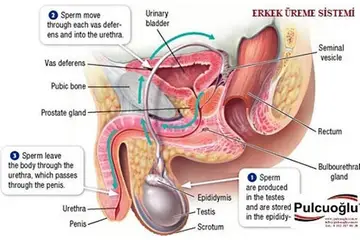

Genital tüberkül, tüberküloz hastalığına neden olan Mycobacterium tuberculosis bakterisinin yol açtığı genital sistemdeki enfeksiyonları ifade eder. Genital tüberküloz, genellikle akciğer tüberkülozunun bir komplikasyonu olarak ortaya çıkar; ancak, primer genital enfeksiyonlar da mümkündür. Bu makalede, genital tüberkül türleri ve özellikleri detaylı bir şekilde ele alınacaktır. Genital Tüberkül Türleri Genital tüberkül, çeşitli alt türlere ayrılabilir. Bu türler, enfeksiyonun yerleşim yeri ve hastalığın seyrine göre değişiklik göstermektedir. Aşağıda, genital tüberkül çeşitleri ve özellikleri sunulmuştur: